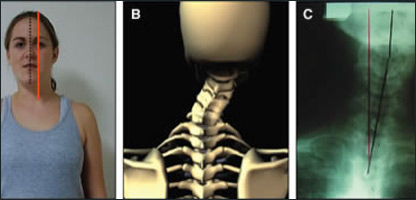

د هر انسان سر له څلورو تر پنځو کيلو ګرامو پوري وزن لري چې، د دې نسبتا درانده وزن پورته کول د شمزۍ او د غاړې د مريو دنده ده.

که چېري موږخپله غاړه نېغه ونيسو نو دغه وزن د غاړې پر مريو او د وجود پر نورو عضلاتو مساوي وېشل کېږي او غاړه په اسانه توګه خپله دنده ترسره کوي.

که چېري مو غاړه د اوږده وخت لپاره ټيټه نيولې وي، بيانو د غاړې پر نازک جوړښت زور راځي او د غاړې د مريود بې ځايه کېدو لامل ګرځي.

د غاړې د مريو د بې ځايه کېدو د مخنيوي لپاره بايد په هرحالت کې غاړه نېغه ونيسو.

د غاړې پر مريو د سر وزن راځي، ځکه بايد له غاړې سره احتياط وکړو.

روغتيايي کارپوهان وايي : د غاړې د مريو د بې ځايه کېدو د مخنيوي لپاره بايد په هرحالت کې غاړه نېغه ونيسو، که په ناسته، په ولاړي او يا په تګ کې وي.

سر بايد داسې ونيول شي چې له وجود سره هيڅ زاويه ونه لري. دغه ډول ورزش هم د غاړې عضلات قوي او غښتلي کوي . ډاکټر هود خېل وايي: